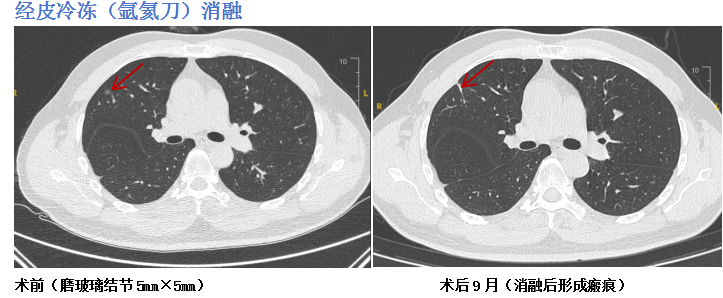

面对不同的结节特性,团队拥有一个丰富的“消融技术武器库”,包括射频消融、微波消融、激光消融、冷消融(氩氦刀)及热蒸汽消融等。